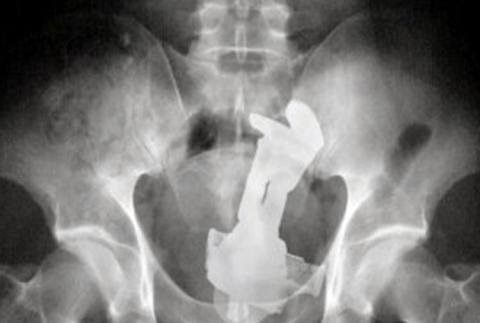

Одним из лидеров недели в Twitter стал хештег #WeirdThingsToPutUpYourAss (Странные штуки, которые суют в задницу). Проктологи со всего мира поделились рентгеновскими снимками содержимого анусов своих пациентов. Выяснилось, что огурец - еще не самое удивительно, что можно обнаружить там, где не светит солнце.